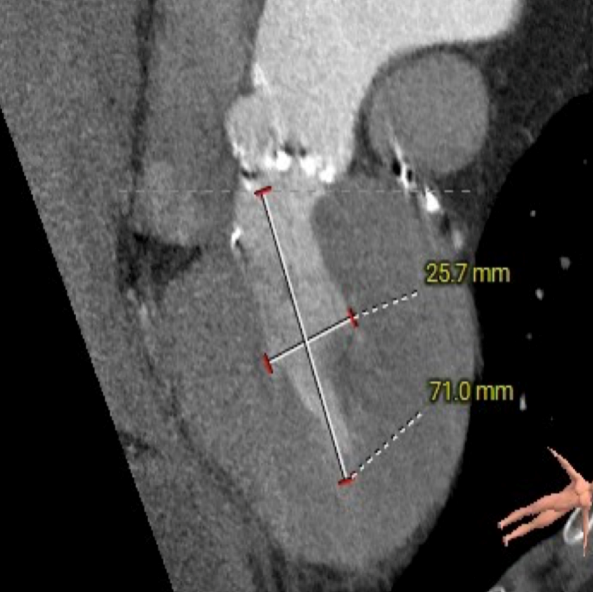

主动脉根部测量

ANNULUS

SOV DIAMETER

LVOT

STJ

ASCENDING AORTA

LEFT VENTRICLE

CT数据显示该患者为Type0主动脉瓣。

主动脉瓣瓣环周长97.1mm,平均周长径 30.9mm,SOV:34.8mm*47.5.3mm*42.4mm,瓣叶增厚,瓣上钙化分布不均,瓣环水平夹角66°。

冠脉高度测量

LEFT CORONARY

左冠开口高度20.4mm

RIGHT CORONARY

右冠开口高18.8mm

钙化分布:HU850钙化积分881mm³